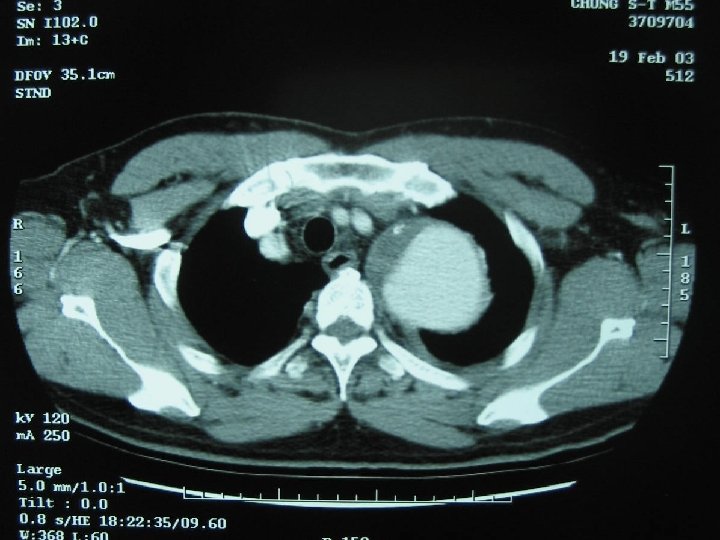

Case w 55 y/o male, HTN for 20+ years with regular medical control for 5 years w Chronic dissecting aortic aneurysm type III noted for 5 years w Left chest pain for 1 week w Denied other systemic diseases w Laboratory data: within normal range

Case w Normal screening spirometry w 2 -D echocardiography: dilated aortic root(diameter 63 mm) & LA, mild MR, good LV contractility w Planning: 1. Left post-lat thoracotomy 2. Femoralfemoral CPB 3. Hypothermia with circulation arrest and retrograde cerebral perfusion via high CVP 18~20 mm. Hg by femoral artery perfusion and partial clamp of venous drain tube 4. Restore proximal aorta perfusion after proximal anastomosis through graft cannulation 5. Open distal anastomosis